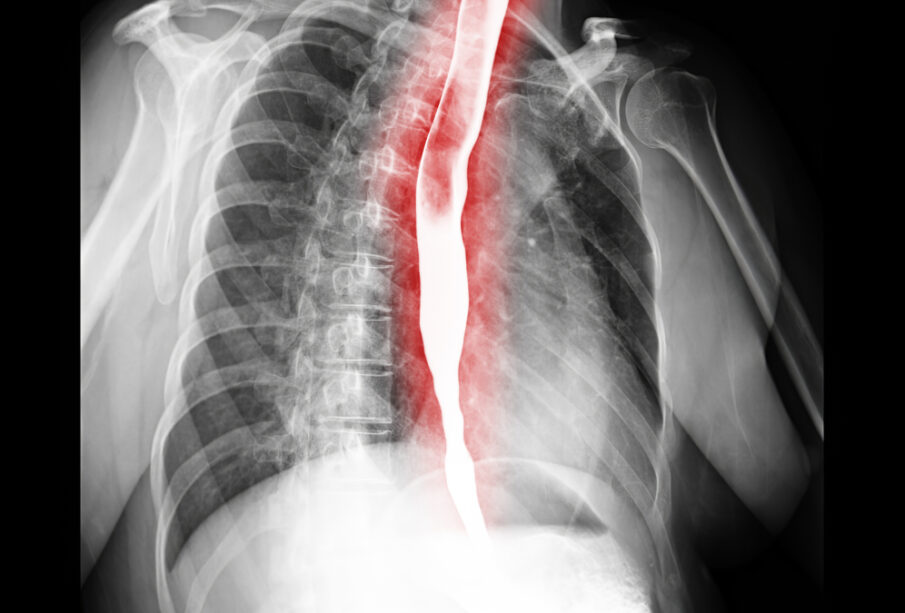

- Bario kontrasto rijimo tyrimas – pacientas išgeria tirštą kontrastinę medžiagą, kuri keliaudama stemple leidžia rentgeno nuotraukose tiksliai matyti siauresnes vietas.